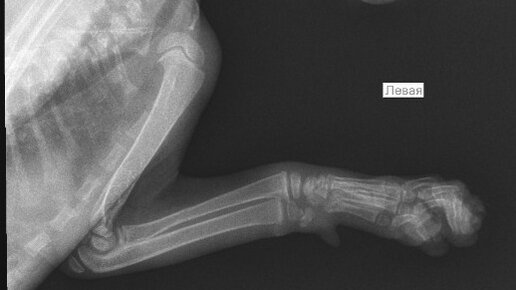

Доброго времени суток! Котенку 2 месяца, вчера поздно вечером случайно прижали дверью (не заметили как прошмыгнул), котенок сильно испугался и начал поджимать левую переднюю лапку. Наощупь серьезных повреждений не обнаружили, котенка успокоили и уложили спать. Утром попросил кушать, ковылял на трех лапках, продолжая держать левую переднюю на весу. Потом ближе к обеду разыгрался, бегал, прыгал и гонял игрушки как обычно. Решили все-таки на всякий случай показать ветеринару. Врач так же наощупь не нашёл ничего серьёзного, но сказал, что не нравится запястье, отправил на рентген...